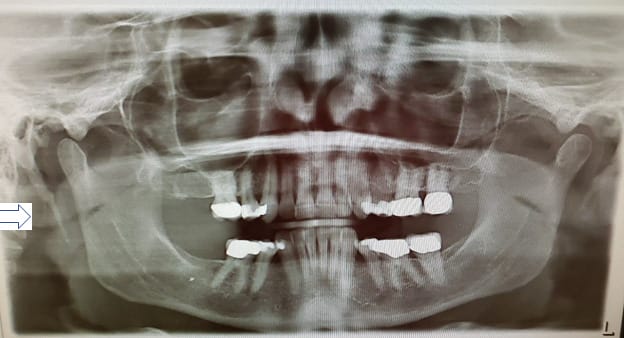

A thorough examination through physical evaluation and imaging is needed to eliminate other conditions and confirm eagle syndrome. To firmly confirm eagle syndrome is through imaging within the standard protocol through radiographs or CT. In dentistry, it can be seen on a panoramic radiograph (see Figure 1) and then referred to their physician for further evaluation.